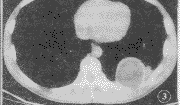

CT检查:左下后胸腔内见一6.2 cm×5.0 cm大小的类圆形囊性包块自后胸壁突向肺叶,密度均匀,CT值1~8 HU;边缘清晰锐利,囊壁呈一均匀致密的环形影,后缘紧贴后胸壁,内侧与胸壁以锐角相交,外侧缘与胸壁成钝角相交,相应部位胸膜肥厚,周围肺叶内未见异常密度灶。骨窗示邻近肋骨受压改变,无骨质破坏(图3)。

图1,2 胸部后前位及左侧位片,左下肺野见椭圆形肿块,心缘遮盖征阴性;侧位片示肿块与脊柱重迭 图3 肿块自后胸壁突向肺叶,边缘清晰,密度均匀,呈水样密度, http://www.100md.com